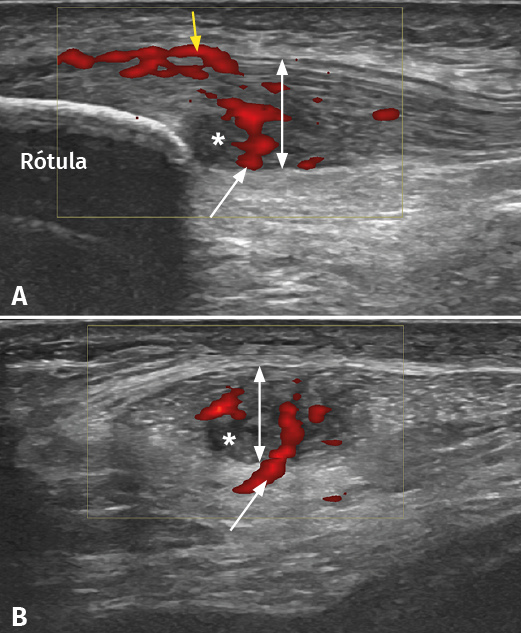

Figure 2. Ultrasound study of proximal patellar tendinopathy. A: longitudinal view of the patellar tendon; B: cross-sectional view of the same tendon. The white arrow shows hypervascularization from Hoffa's fat pad, while the yellow arrow indicates the increase in vascularization at surface (bursa) level. The double white arrow shows the increase in tendon thickness accompanied by hypoechogenic tissue degeneration zones (asterisk).

It has been demonstrated that both colour Doppler ultrasound (CD-US) (Figure 2) and MRI (Figure 3) are useful tools for confirming the diagnosis and can orientate treatment(10). Over the last two decades, ultrasound tissue characterization (UTC) has been developed with the purpose of obtaining even more information than conventional ultrasound. Indeed, the technique has become so important that some authors consider that UTC could be the most important development in medical US imaging since the introduction of Doppler ultrasound(13). Ultrasound tissue characterization is an imaging technique specifically designed for application to tendons. It is based on a colour scale that allows us to determine the degree of elasticity of the tendon tissue, and is able to measure small changes in tendon structure (e.g., as in evaluating the presence of tissue degeneration or fibrosis) - allowing us to establish an early diagnosis that can limit chronification of the process. The technique also has therapeutic applications as a tool for monitoring and guiding ongoing treatments, even after surgical repair, or for measuring the time for returning to physical activity (particularly in top athletes)(14,15).